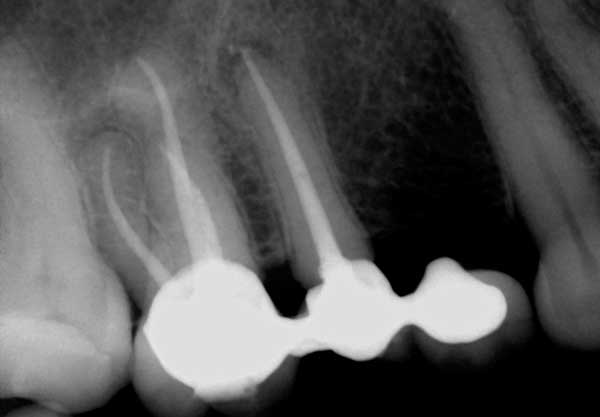

7. Pourquoi certaines pathologies périapicales (PAP) durent-elles plusieurs années après le traitement de canal ?

Certaines radiolucences périapicales (PARL) (figure 4) peuvent durer jusqu’à cinq ans après le traitement de canal. Un facteur qui contribue à la présence prolongée des PARL est la taille de la lésion initiale, de sorte que les lésions plus grandes ont tendance à durer plus longtemps et à guérir à un rythme plus lent. La localisation de la lésion est un autre facteur qui peut contribuer à cette guérison prolongée. Les lésions situées dans un os plus dense, comme la mandibule antérieure, ont tendance à guérir plus lentement que les lésions situées dans un os moins cortical, comme le maxillaire postérieur. Les antécédents médicaux du patient sont un autre facteur à prendre en considération dans de tels cas. Des études montrent que les patients diabétiques, en raison de la baisse de la fonction de leur système immunitaire, peuvent avoir besoin de plus de temps pour guérir. Certains des PAP qui ont tendance à durer peuvent également être des tissus cicatriciels dans l’os.

Figure 4